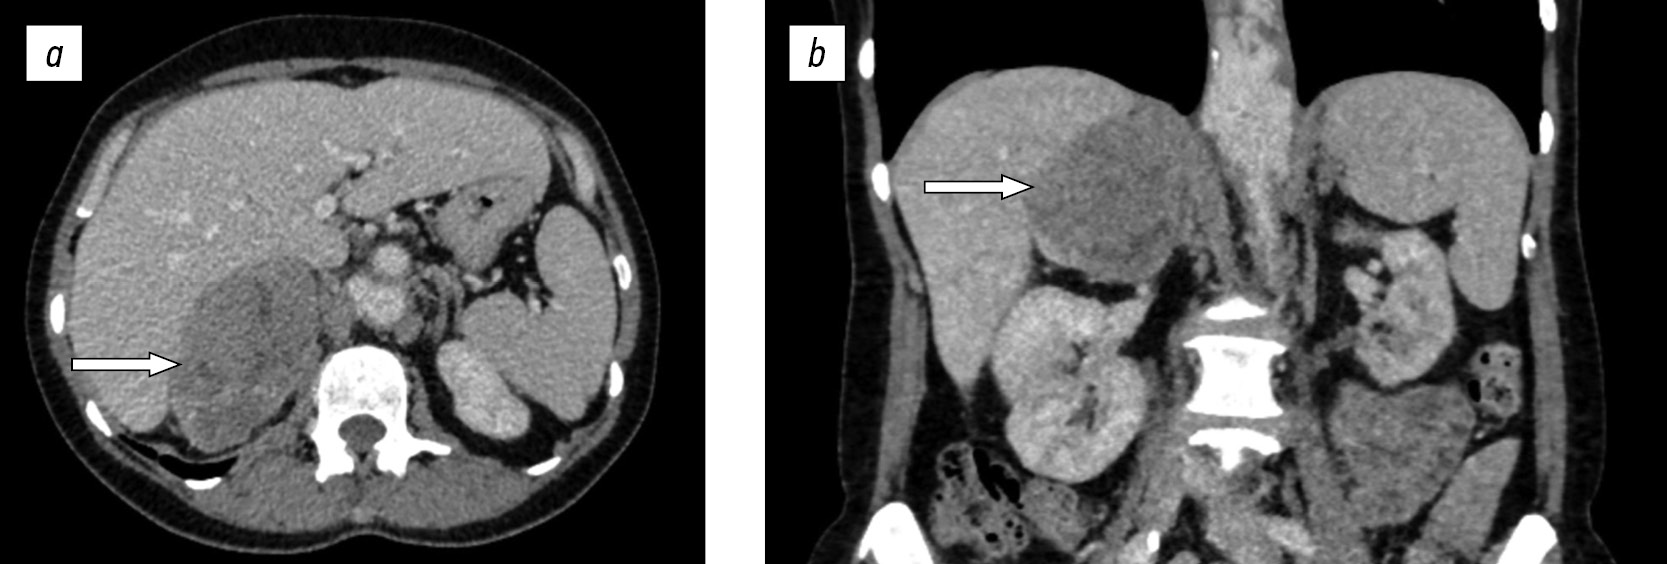

В клиническом анализе крови наблюдали гипохромную анемию (от 84 до 92 г/л), лейкоцитоз (от 10,5 до 24,4 · 109/л), тромбоцитоз (от 419 до 502 · 109/л) и повышение скорости оседания эритроцитов (от 33 до 57 мм/ч). Дополнительно отмечено повышение уровня С-реактивного белка (от 15 до 124,5 г/л). Гормональное исследование не выявило данных, свидетельствующих в пользу феохромоцитомы и первичного гиперальдостеронизма. Суточный ритм кортизола был сохранен. Однако у всех больных было получено повышение уровня кортизола (с 56,8 до 68,7 нмоль/л) на фоне ночного подавляющего теста с 1 мг дексаметазона. Уровень дегидроэпиандростерона-сульфата был снижен (от 0,19 до 0,28 мкг/мл). По данным высокоэффективной жидкостной хроматографии сыворотки крови, отклонения значений не выявлены. По результатам компьютерной томографии органов брюшной полости и забрюшинного пространства с контрастированием, в проекции правого надпочечника определялось объемное образование размерами от 10 до 17см, с деформацией окружающих тканей, со смещением правой почки (в одном случае с подозрением на инвазию в нижнюю полую вену), неоднородной структуры (с участками кистозной трансформации), с высокой нативной плотностью (максимально до +45 HU) и абсолютным коэффициентом вымывания контрастного вещества через 15 мин от 20 до 48 %. То есть такие случайно выявленные опухоли имели злокачественный интраскопический фенотип, что на предоперационном этапе было расценено как адренокортикальная карцинома (рис. 1).

Рис. 1. Компьютерная томография органов брюшной полости и забрюшинного пространства с контрастированием у больной 55 лет с синовиальной саркомой забрюшинного пространства справа: а — аксиальная плоскость, паренхиматозная фаза; b — корональная плоскость, паренхиматозная фаза

Fig. 1. Computed tomography of the abdominal and retroperitoneal area with contrast of a 55-year-old patient with synovial sarcoma of the retroperitoneal area on the right side: a, axial plane, enhanced phase; b, coronal plane, enhanced phase